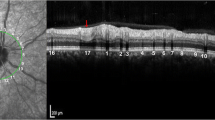

Careful identification of venous and arterial vessels was performed on cSLO images according to anatomical features before various measurements. On the images, compared with arteries, the veins have two wider dark layers (plasma layers) on both sides of a narrower visible light-reflex centerline (Fig. 1a).

cSLO image and measurement methods of various vascular geometric parameters. The cSLO image was acquired by the circular scan mode with four overlaid concentric circles. Compared with arteries (white asterisk), veins are thicker and darker and have a narrower light luminal reflex (blue asterisk). Zone A [0–0.5 disc diameter (DD) from the optic margin], zone B (0.5–1.0 DD from the optic margin), and zone C (0.5–2.0 DD from the optic margin) are labeled. b–d Magnified cSLO image (white box in a). The white arc represents the vessel branch angle. b Method 1 (vessel reflex to vessel reflex): all three measurement points (dots on the yellow line) are on the vessel reflex, two on the daughter’s vessels (blue arrow), and one on the parent vessel (green arrow). c Method 2 (plasma layers to plasma layers): all three points are on the plasma layers. d Method 3 (plasma layers to vessel reflex to plasma layers): two points are on the plasma layers, and one is on the luminal reflex. e–g Magnified cSLO image (blue box in a). The measurement of retinal vessel diameter and vessel tortuosity. e Positioning a through-line along the lumen. f The automatic generation of the cross-line perpendicular to the vessel with prespecified 10 μm space calculates vessel diameter on the basis of an intensity profile algorithm. g The blue line represents the actual length, and the white line the shortest length. h Fractal dimension within zone C after binarization and skeletonization

All measurements were performed using ImageJ software (version 1.8.0) by two ophthalmologists, who assessed all images independently. The characteristics of subjects were blinded to the two operators. All images were sharpened and magnified to 200–300% using ImageJ before measurement to improve the recognition of vascular details. For evaluating BA, vessel diameter, and vessel tortuosity, vessels in the superotemporal quadrant were analyzed first; if the vessels could not be measured due to brightness or artery–vein intertwining, then the corresponding vessels in the inferotemporal quadrant would be selected for measurement. The supero- or inferotemporal quadrant was selected because vessels within the quadrant could be more reliably identified [11]. Furthermore, vessel diameter and vessel tortuosity were measured in zone B [the region 0.5–1.0-disc diameter (DD) away from the disc margin] and Df was measured in zone C (the region 0.5–2.0 DD away from the disc margin). The parameters and corresponding measuring tool/macro/plugin are described in the following corresponding sections.

The BA of the first branch was analyzed using the Angle Tool of ImageJ. To the best of our knowledge, there was no reported protocol for BA measurements using cSLO images; hence we first tested the performance of three prespecified methods: method 1 (vessel reflex to vessel reflex), method 2 (plasma layers to plasma layers), and method 3 (plasma layers to vessel reflex to plasma layers) (Fig. 1b–d). Measurements from each method were performed three times to average the values to improve precision. After assessing the measurement performance (repeatability and reproducibility) among the three methods, the method with the highest performance was selected for the study.

The main purpose of the present study is to verify the feasibility of using cSLO for measuring various geometric parameters. To the best of our knowledge, this is the first research applying cSLO to comprehensively measure the four most studied vascular geometric parameters. For image acquisition, a built-in scanning module, namely the circular scan, for the routine measurement of peri-optic nerve thickness was used. As one of the most clinically applied modules, the circular scan is high-speed and can acquire high-quality images within seconds. The acquired cSLO images were preprocessed in advance before various assessments (the images were enlarged to 200–300% times and sharpened using ImageJ) to show the boundaries and details of vessels more clearly. As the preprocessed images were more helpful for identifying vessel boundaries and luminal centerline, this setup is recommended for future studies manually analyzing vascular geometry using cSLO images.

In our study, Df was measured within a predetermined area (zone C), as in previous studies using FP; however, the angle of a default cSLO image is 30°, significantly smaller than the 45° image using a conventional fundus camera. For the acquired cSLO image aided by the internal fixation target, the optic disc is not perfectly centered in the image but slightly towards the nasal quadrant (Fig. 1a). Therefore, analysis of vascular geometry within zone C using cSLO images would encounter nasal quadrant missing data. However, the impact of missing data could be contained because of a constant scanning configuration. Future studies could acquire cSLO images with the optic disc well centered by adjusting the external fixation target; however, the internal fixation target is built into the OCT machine, and thus more consistent and applicable to a clinical context. Therefore, narrowing the analyzed region (such as performing Df measurements at the region 0.5–1.5 DD from the optic margin or zone B instead of zone C) might be another option.